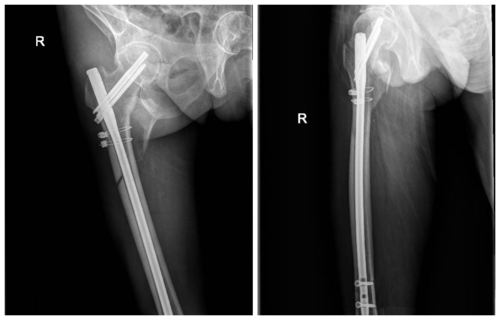

患处行CT三维重建后发现,骨折程度复杂,骨折类型为股骨大小转子均发生明显移位的Tronzo-Evans分型Ⅳ型粉碎性骨折,且骨折线累及股骨转子下。常规髓内针假体长度不足以维持复位后骨折端稳定,且患者多年强直性脊柱炎导致脊柱后凸畸形严重,无法保持平卧,术中卧位选择也是无法避免的一个难题。对于该患者手术卧位、手术方式以及假体选择,孟祥海专家团队充分进行术前讨论,最终决定使用加长柄髓内钉假体进行固定,并且对骨折断端复位后进行钛缆加强固定。10月9日,孟祥海副主任医师带领刘照睿副主任医师、张英副主任医师、杜闫圻医师顺利完成了右股骨转子间骨折闭合复位髓内钉内固定术,术后安返病房。

*术后X片

术后刘照睿副主任医师及时评价患者状态,指导其在床上康复锻炼,患者在床上活动可,家属更加容易进行翻身护理。患者及家属对我院围手术期细心准备、耐心答疑解惑以及精湛手术技术赞不绝口。